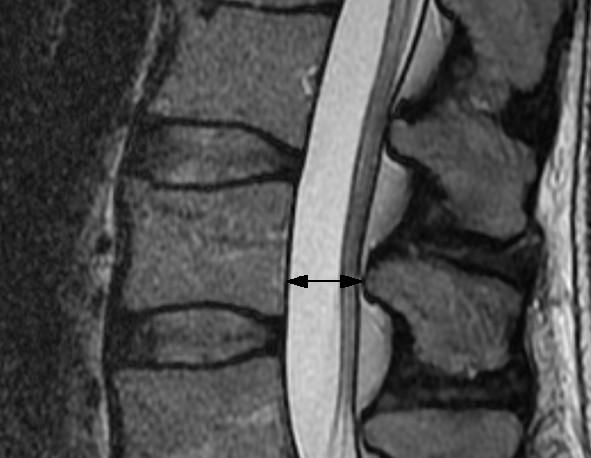

25 studies reporting on radiological signs of LSS and four systematic reviews related to the evaluation of different treatments were found. Ten different parameters were identified to quantify lumbar spinal stenosis. Most often reported measures for central stenosis were antero-posterior diameter (< 10 mm) and cross-sectional area (< 70 mm(2)) of spinal canal. For lateral stenosis height and depth of the lateral recess, and for foraminal stenosis the foraminal diameter were typically used. Only four of 63 primary studies included in the systematic reviews reported on quantitative measures for defining inclusion criteria of patients in prognostic studies.

发现 25 篇报告 LSS 影像学征象的研究和 4 篇与评估不同治疗方法相关的系统评价。确定了 10 个不同的参数来量化腰椎椎管狭窄症。最常报道的中央狭窄测量值为椎管前后径(<10mm)和横截面积(<70mm²)。对于侧方狭窄,通常使用侧隐窝的高度和深度以及椎间孔狭窄的椎间孔直径。在纳入系统评价的 63 项主要研究中,仅有 4 项报告了用于确定预后研究患者纳入标准的定量测量值。